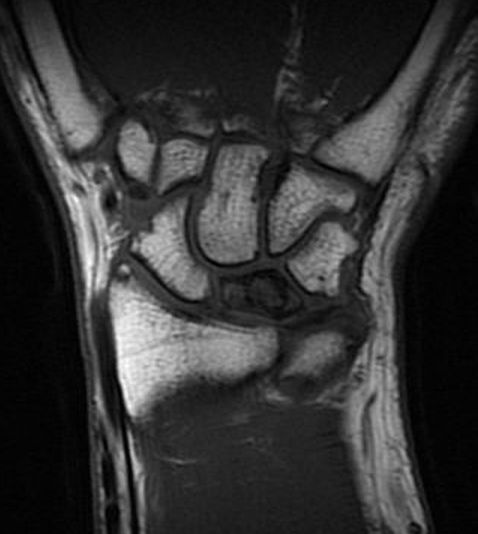

Stadium 3A: Kollapsad lunatum, kapitatum förflyttad proximalt [2]

Slätröntgen och T1-viktad MR-bild av lunatummalaci stadium 3A